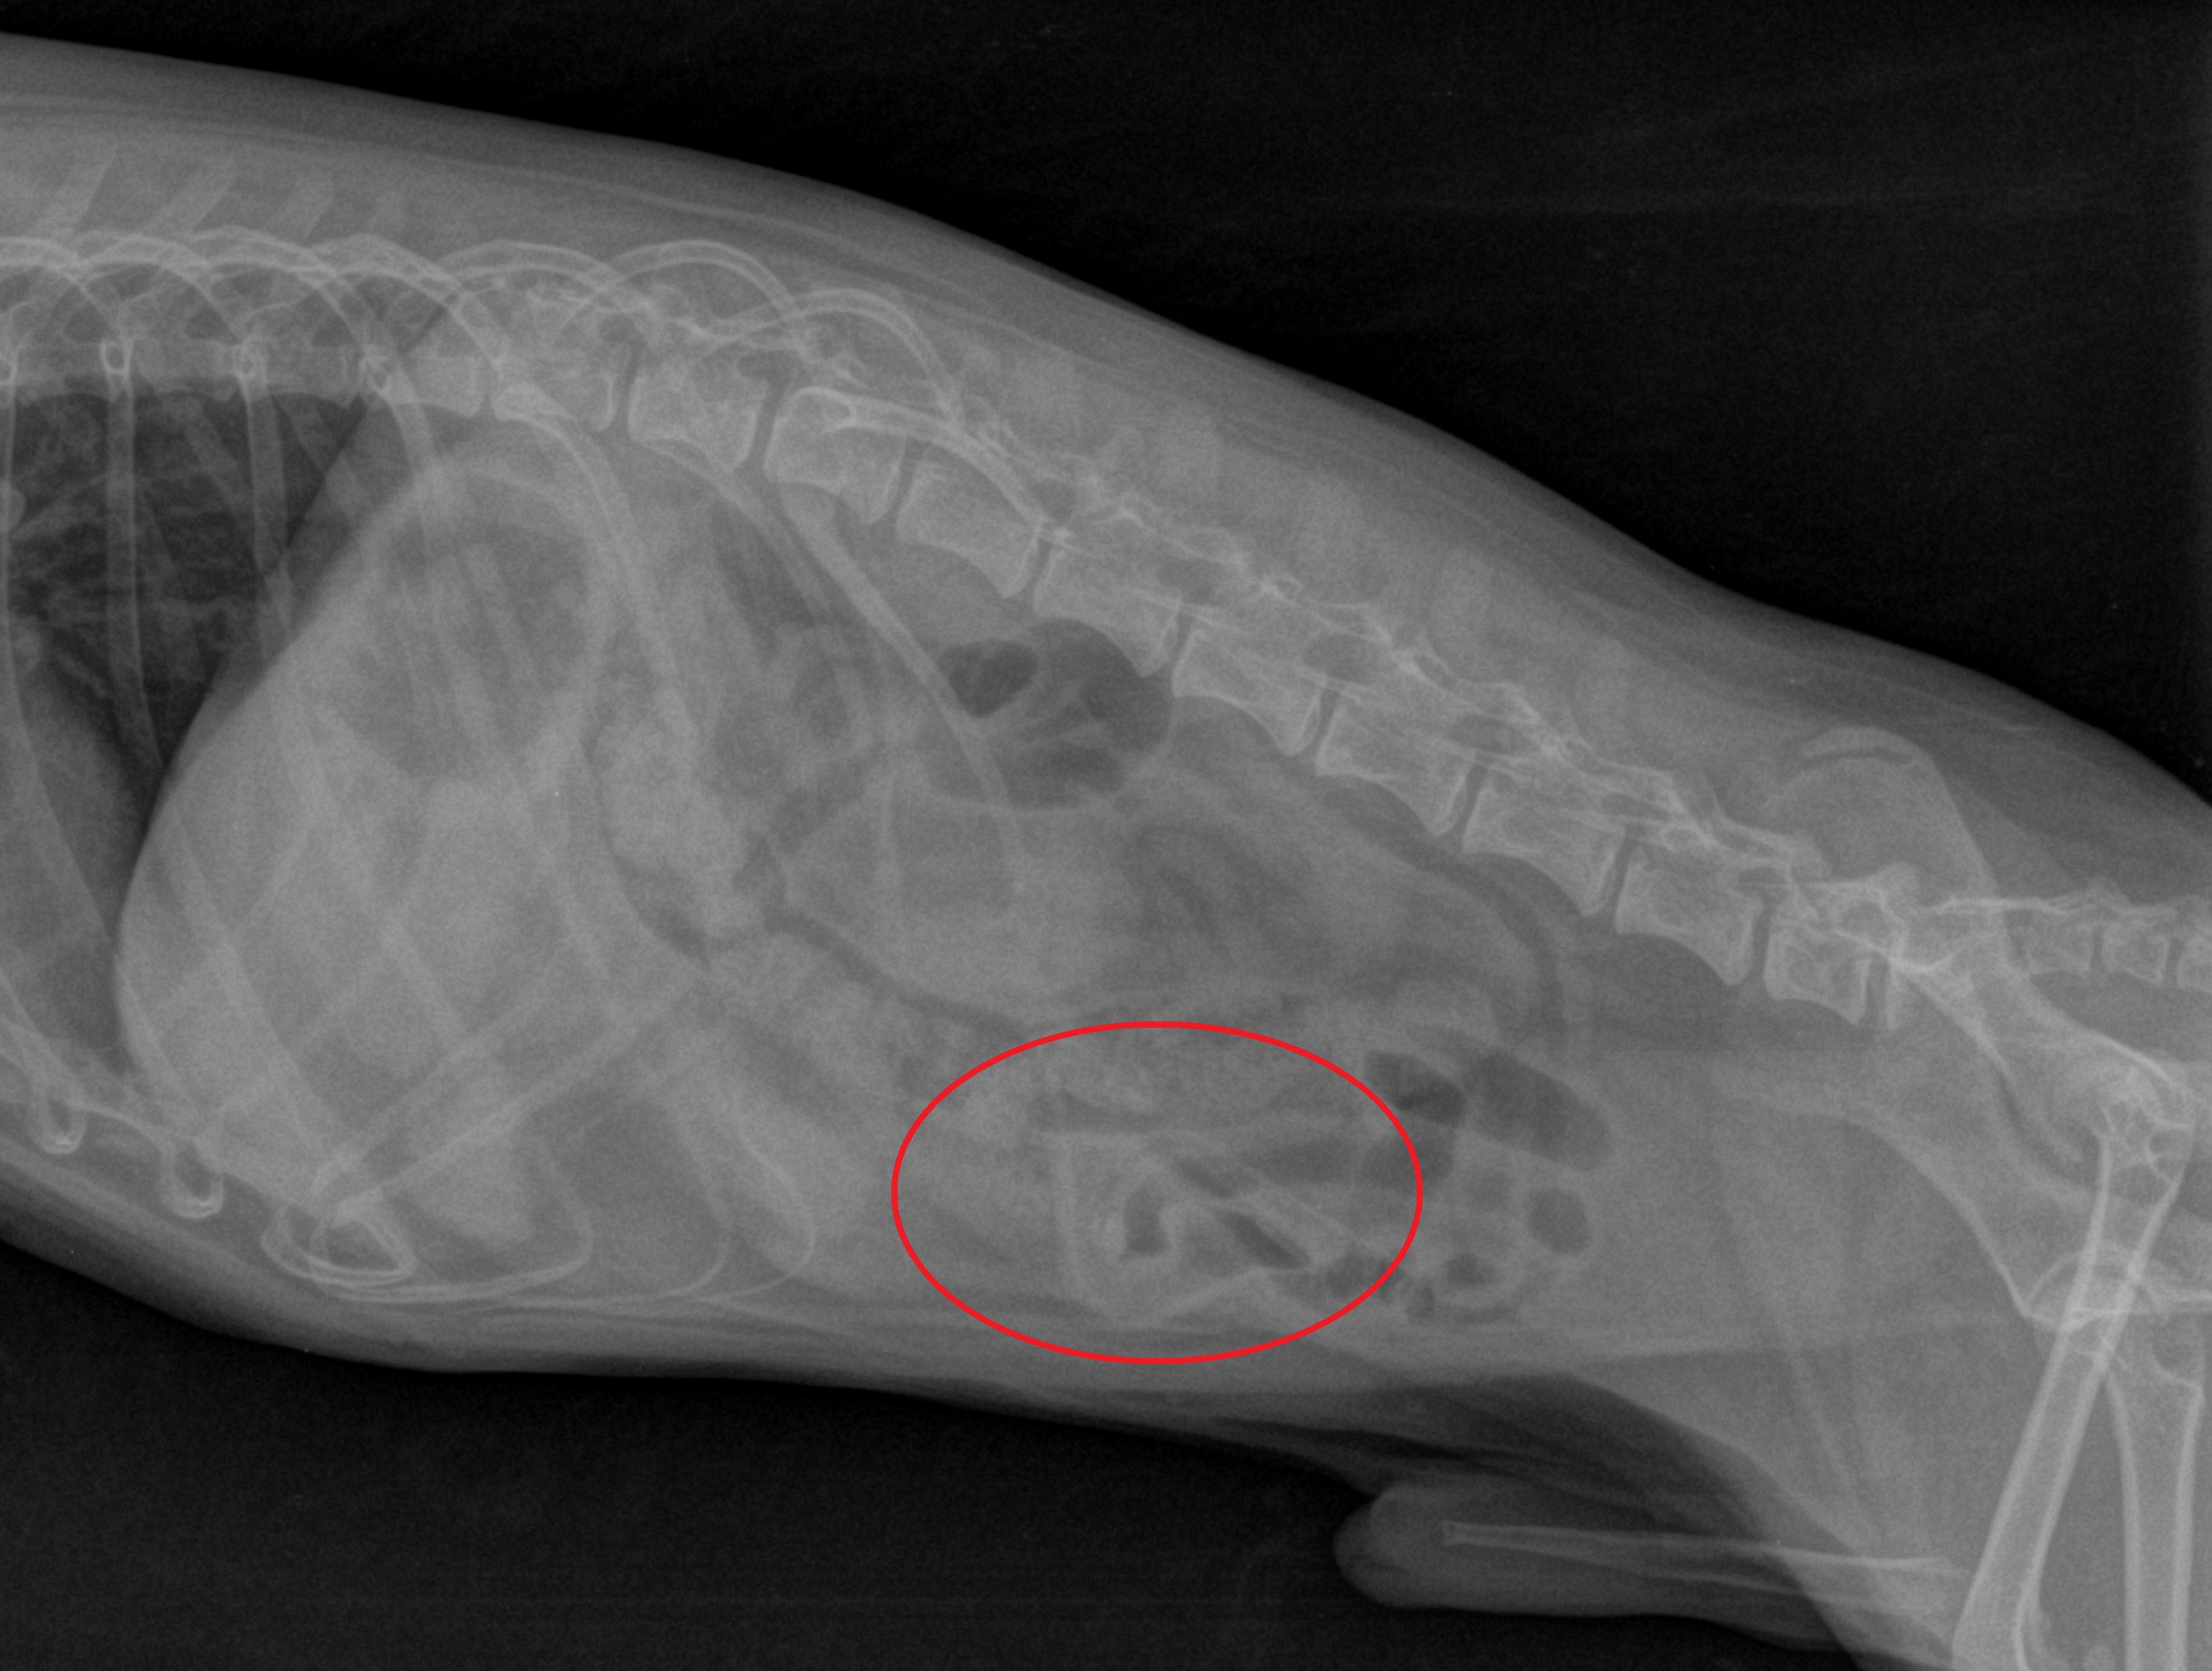

Toto štěně rhodéského ridgebacka začalo být z ničeho nic apatické. RTG dutiny břišní odhalilo neznámé těleso v dutině břišní.

Toto je rentgen dutiny břišní 4 kg maltézského psíka. Cizí těleso jsme podle rtg snímku nedokázali identifikovat.